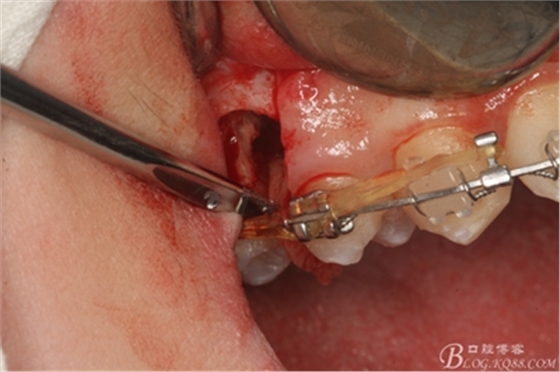

圖8.因16與14合面的間隙僅2mm左右,牙根無法合向脫位,如何考慮15牙根的脫位將是最大問題。高速手機(jī)去除牙間隙內(nèi)的覆蓋在15牙根表面的牙齦組織

圖10.去除牙齦組織后。露出15牙根斷面,合面無法脫位